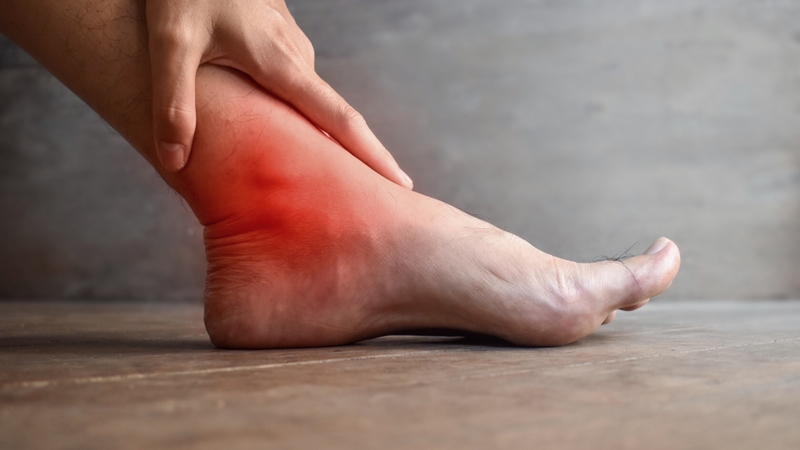

Nhận biết sớm các triệu chứng bong gân để xử lý hiệu quả 1

Đau là triệu chứng bong gân xuất hiện đầu tiên và rõ ràng nhất

Đau do bong gân thường xuất phát từ tổn thương dây chằng, gây kích ứng các đầu mút thần kinh tại vùng bị ảnh hưởng.

Sưng tấy quanh khớp

Sưng là một phản ứng tự nhiên của cơ thể sau chấn thương dây chằng. Dưới đây là những đặc điểm chính của triệu chứng sưng khi bị bong gân. Sưng xuất hiện nhanh chóng, thường trong vài giờ sau chấn thương, kèm theo cảm giác nóng và căng tức quanh khớp. Mức độ sưng phản ánh mức độ nghiêm trọng của tổn thương dây chằng. Ở bong gân nhẹ, sưng có thể chỉ nhẹ và khu trú, trong khi bong gân nặng gây sưng to, lan rộng. Sưng là kết quả của viêm và tích tụ dịch quanh khớp do tổn thương mô mềm.